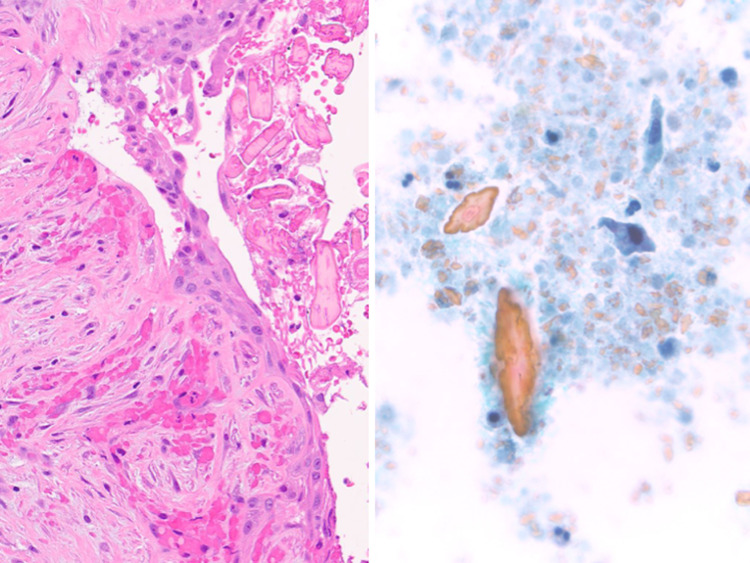

Fig. 2.

Salivary mucocele biopsy showing (left) submucosal mucus extravasation (H&E stain, medium magnification) (upper right) associated with abundant admixed histiocytes (H&E stain, high magnification). (Lower right) Muciphages are CD68 immunoreactive (Immunohistochemistry, high magnification)